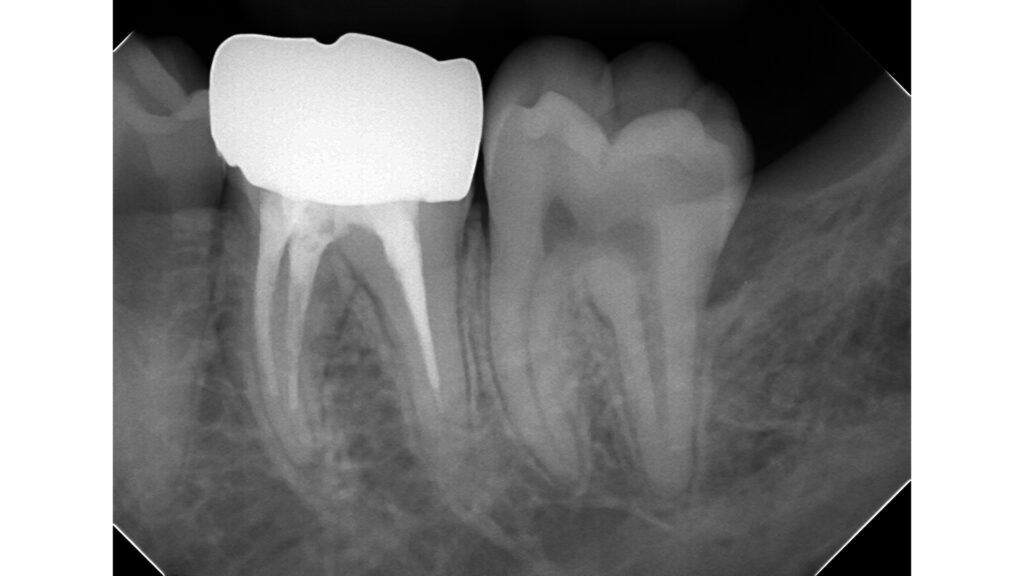

左下奥歯に違和感を訴えて来院されました。

銀歯の周囲に腫れを認めます。

歯周ポケットは深く歯根破折のため抜歯判定となりました。